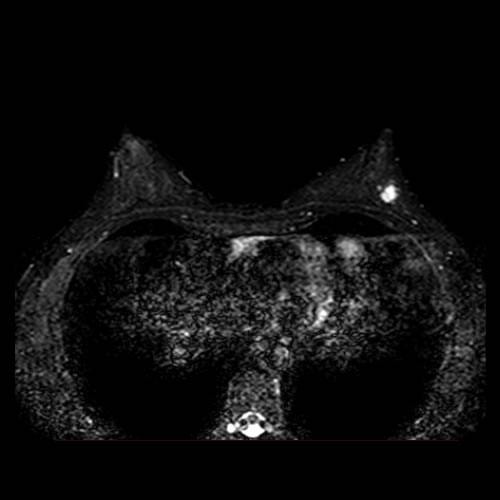

– Sexo femenino

– 50 años

– MC: nódulo autopalpable en CSE MI.

– Examen mamario: dos nódulos en MI, H1 y H2

– PERSONALES: Nódulos bajo control ecográfico